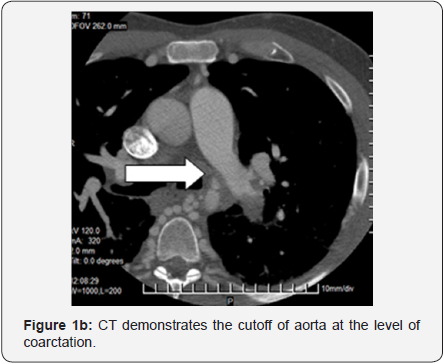

A 37-year-old man presented to the hospital with sudden onset of chest discomfort and shortness of breath. He was found to have atrial fibrillation, and pulmonary edema. The patient had similar episodes of AFib and angina pectoris in the past,but had never received a cardiac catheterization. A cardiac catheterization through the femoral artery was attempted and aborted due to complete occlusion of thoracic aorta. The cardiac catheterization was completed through the brachial artery, which demonstrated severe, diffuse multi-vessel coronary artery disease and severe left ventricular hypertrophy with an ejection fraction of approximately 50%. Further diagnostic workup during this admission revealed coarctation of the aorta (CoAo) with near complete interruption of the distal arch and proximal descending aorta on chest CT (Figure 1a). His Chest X-ray demonstrated the usual collaterals via mammary arteries to intercostal arteries with subsequent formation of “fish ribs” (Figure 1b). Echocardiography showed left atrial enlargement and marked thickening of left ventricular walls. Given the constellation of problems including severe left ventricular hypertrophy, which makes myocardial protection difficult, the decision was made to undertake a two-stage surgical approach. The patient underwent coronary artery bypass grafting through median sternotomy followed by repair of CoAo through left lateral thoracotomy 8 weeks later.